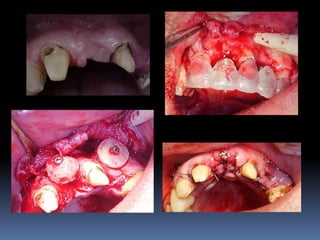

Atrofias ósseas

•Procedimentos de enxertia óssea para

restabelecimento de dimensões perdidas

•Compensações dos tecidos perdidos nas

próteses

Guia cirúrgico

•Permite o posicionamento ideal da fresagem

através de orifício em guias transparentes

•Utilização de tubos, cones ou somente orifícios

realizados por fresas

•Liberdade controlada da fresa